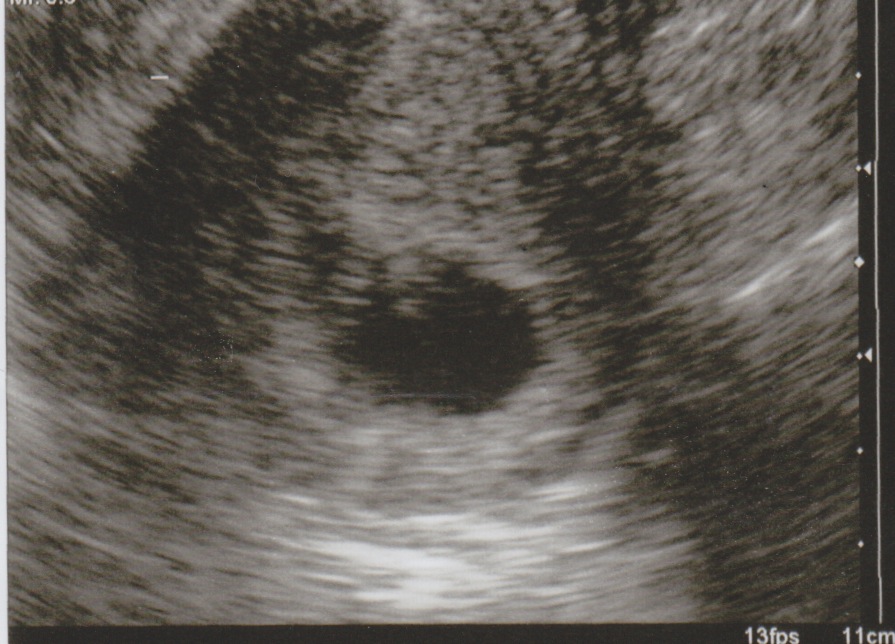

and here is my dating scan at 12 weeks

Attachment 18833

Sorry no nub shots but predictions welcome

The nub is on there and I'll lean girl although there is a bump on top that's throwing me off so wouldn't be suprised either way!!

Thanks for your guesses, just to let you know you were all correct! Its a girl :D